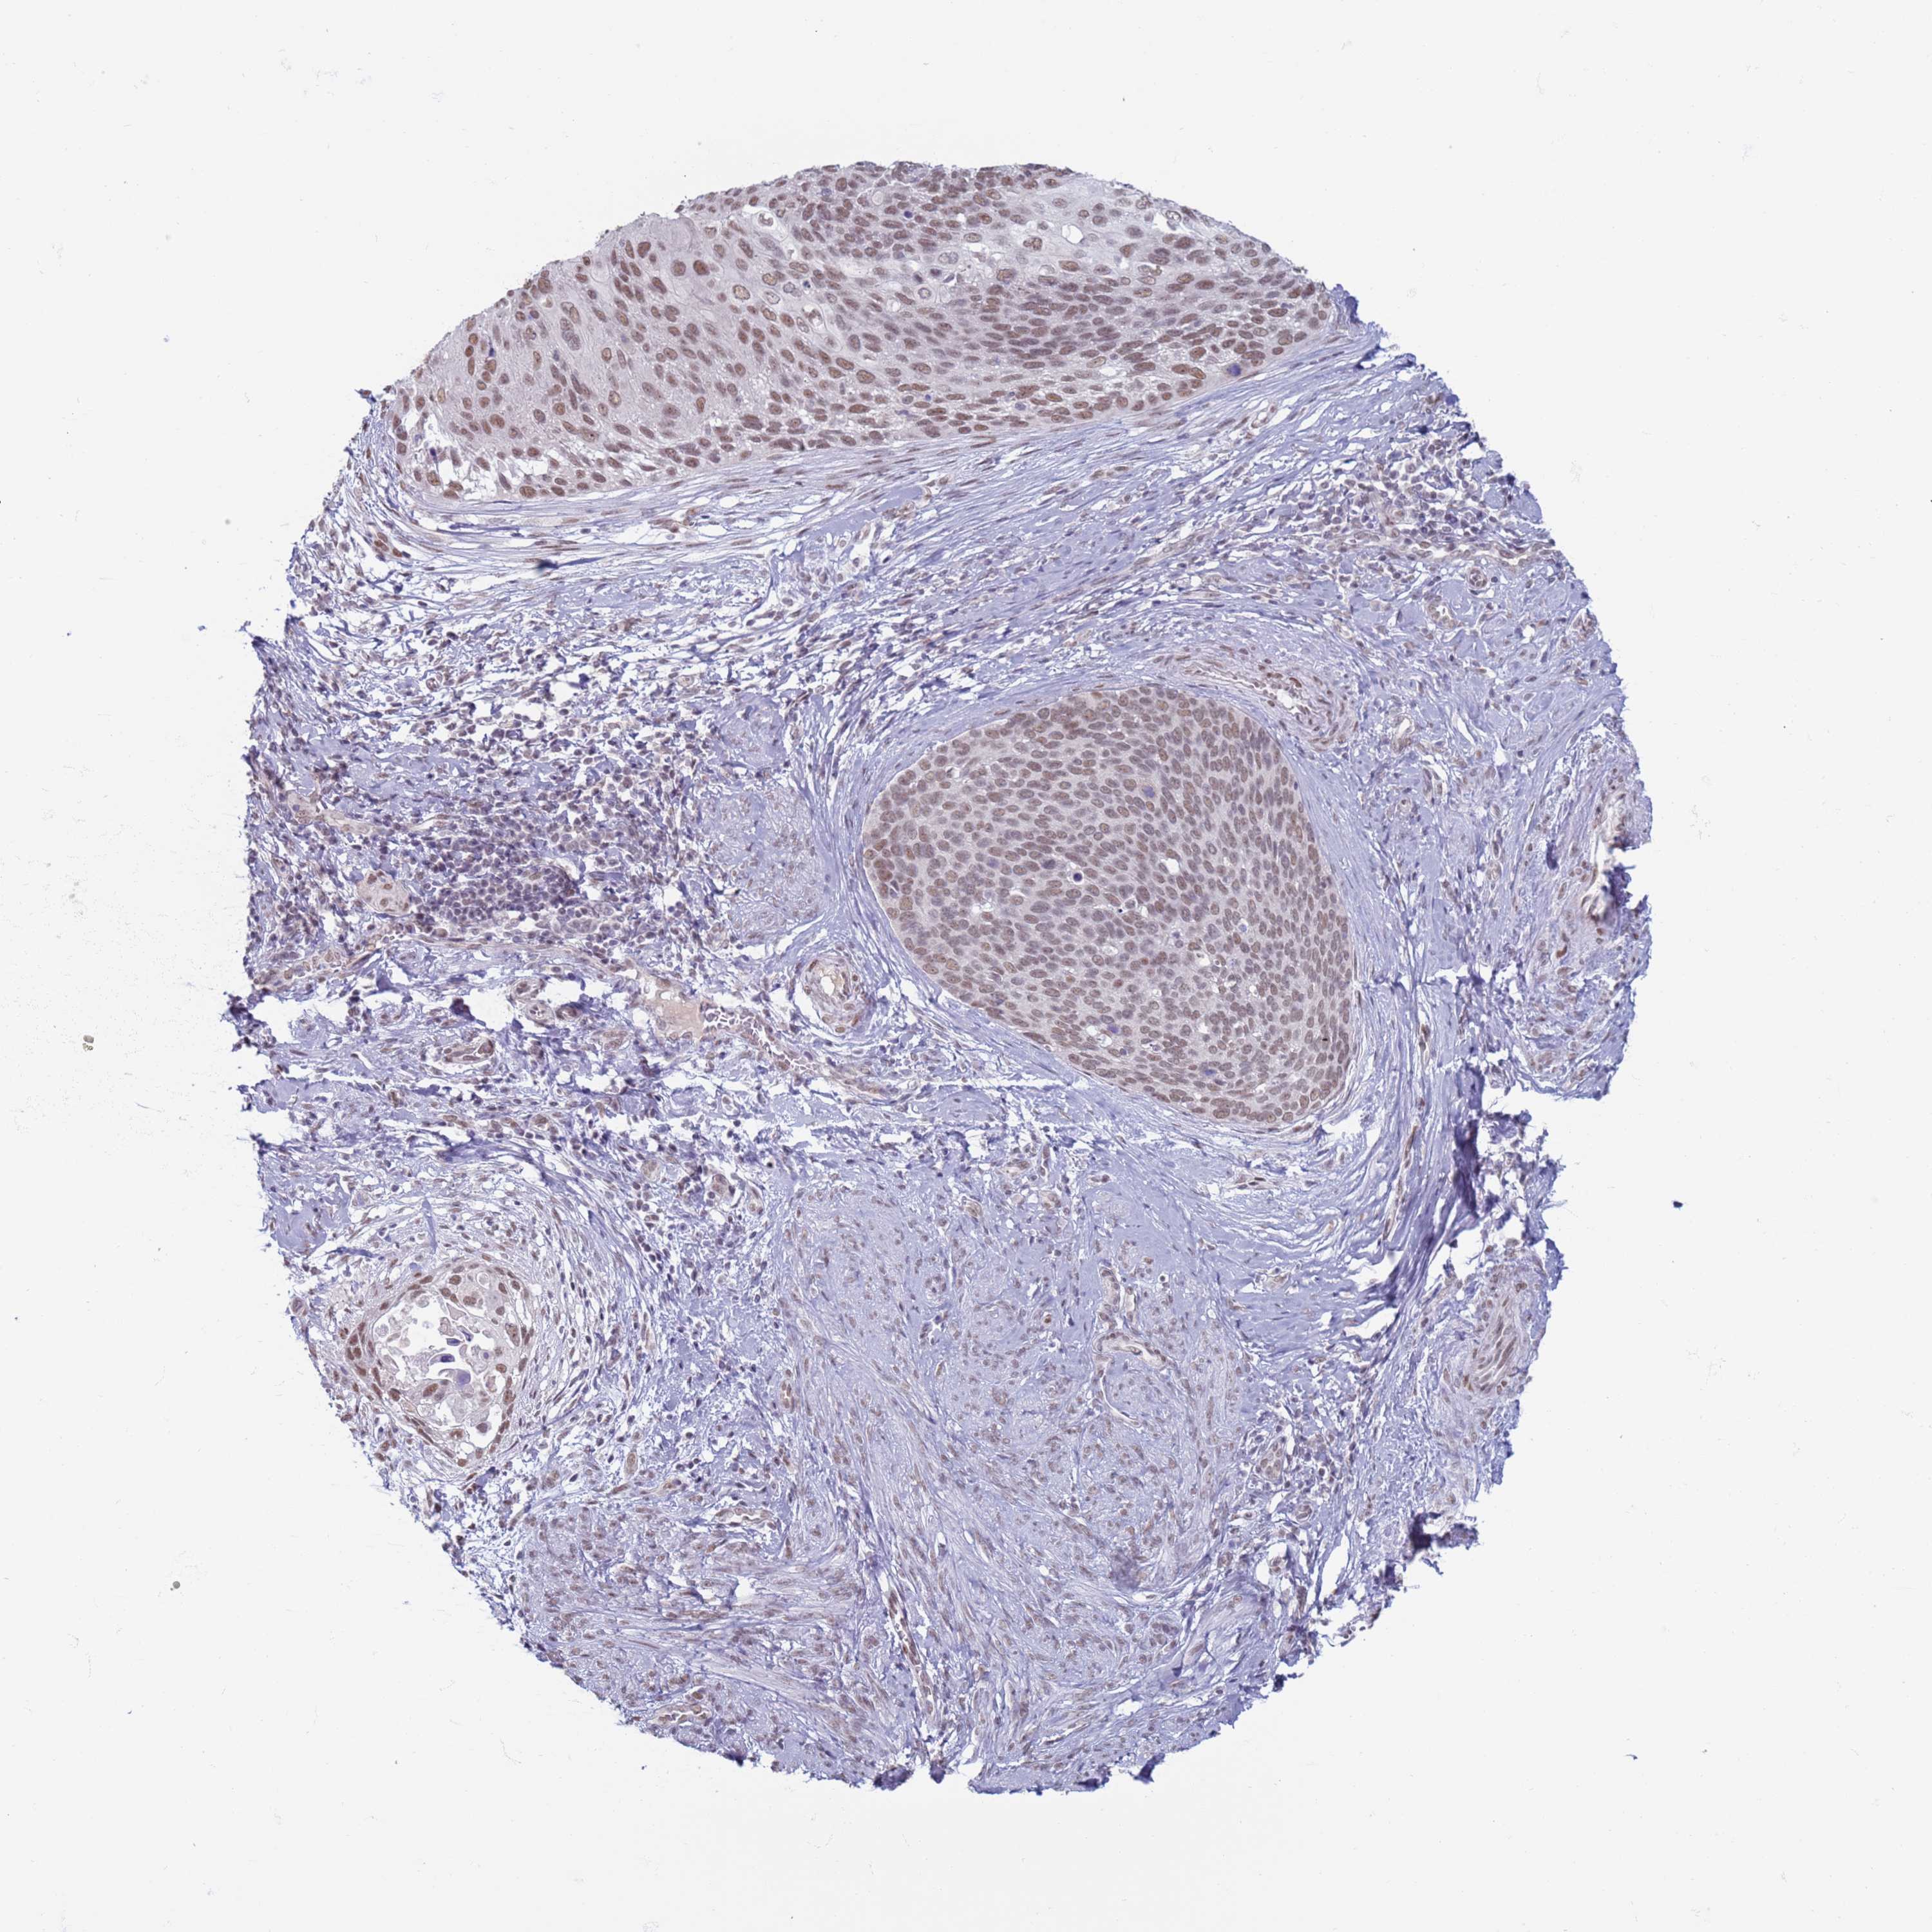

CERVICAL CANCER - Protein expressioni

A mouse-over function shows sample information and annotation data. Click on an image to view it in a full screen mode. Samples can be filtered based on level of antibody staining by selecting one or several of the following categories: high, medium, low and not detected. The assay and annotation is described here.

Note that samples used for immunohistochemistry by the Human Protein Atlas do not correspond to samples in the TCGA dataset.

Antibody stainingi

Antibody staining in the annotated cell types in the current human tissue is reported as not detected, low, medium, or high, based on conventional immunohistochemistry profiling in selected tissues. This score is based on the combination of the staining intensity and fraction of stained cells.

Each image is clickable and will lead to virtual microscopy that enables deeper exploration of all samples and also displays staining intensity scores, fraction scores and subcellular localization as well as patient and tissue information for each sample.

Antibody HPA041906

Antibody HPA043552

Staining

High

Medium

Low

Not detected

Intensity

Strong

Moderate

Weak

Negative

Quantity

>75%

75%-25%

<25%

None

Location

Nuclear

Cytoplasmic/membranous

Cytoplasmic/membranous,nuclear

Squamous cell carcinoma, NOS

Adenocarcinoma, NOS